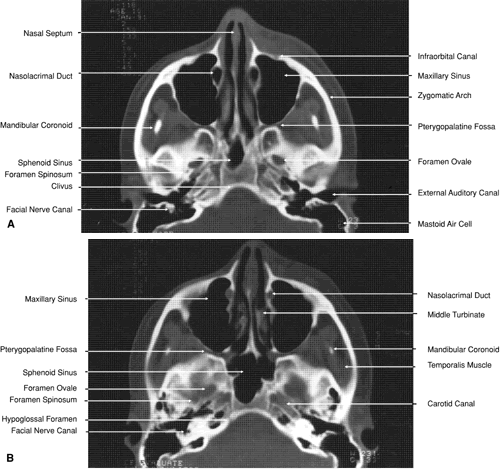

The globe is shown in Figure 12. The orbit and periorbital structures are shown in Figures 13 through 16, and the optic canal is shown in Figures 17 through 26. The cavernous sinus and optic chiasm are shown in Figures 27 and 28, and the posterior visual pathway and cranial nerves are shown in Figures 29 through 33.

Fig. 29. A. Axial computed tomography soft tissue image at the level of the base of skull. B. Axial computed tomography bone window image at the level of the base of skull.